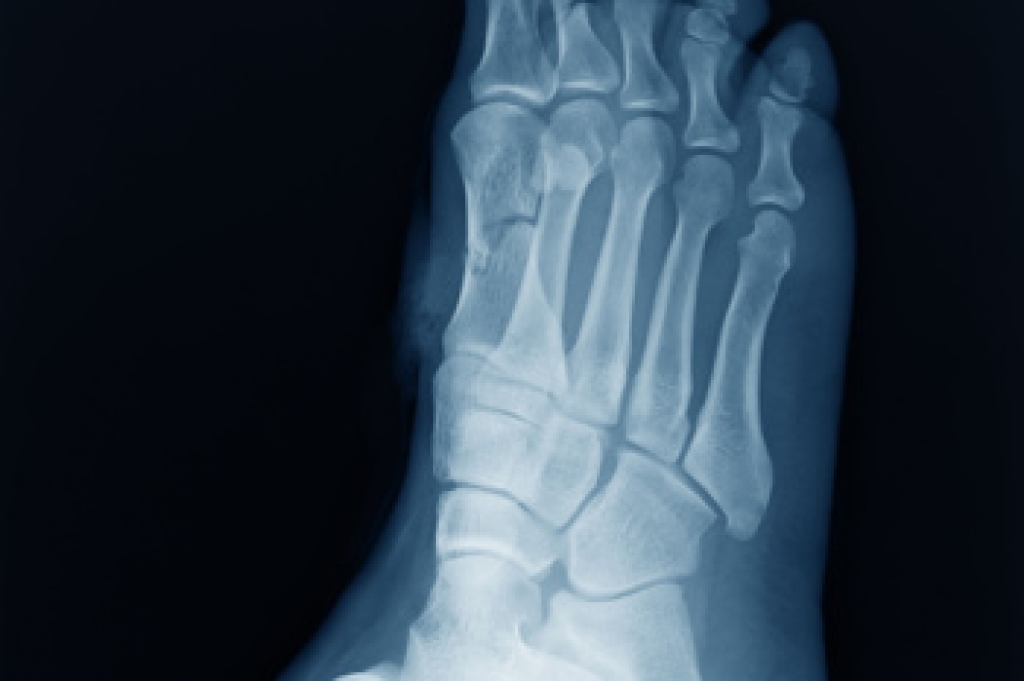

In many cases the cause of toe pain is obvious, but in others, a podiatrist may want to use more advanced methods to determine the problem. These can range from simple visual inspections and sensation tests to X-rays and MRI scans. Prior medical history, family medical history, and any recent physical traumatic events will all be taken into consideration for a proper diagnosis.

Due to the wide variety of potential causes of ankle pain, podiatrists will utilize a number of different methods to properly diagnose ankle pain. This can include asking for personal and family medical histories and of any recent injuries. Further diagnosis may include sensation tests, a physical examination, and potentially x-rays or other imaging tests.

Diagnosis

Diagnosis of cuboid syndrome is often difficult, and it is often misdiagnosed. X-rays, MRIs and CT scans often fail to properly show the cuboid subluxation. Although there isn’t a specific test used to diagnose cuboid syndrome, your podiatrist will usually check if pain is felt while pressing firmly on the cuboid bone of your foot.